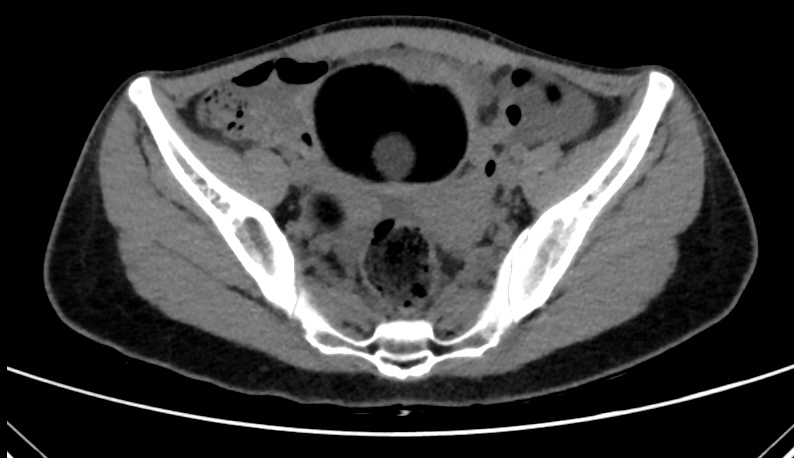

La TC abdominal mostró cuatro lesiones anexiales bien delimitadas, con predominio de contenido graso y nódulos murales calcificados, altamente compatibles con teratomas ováricos bilaterales, sin líquido libre en ese momento.